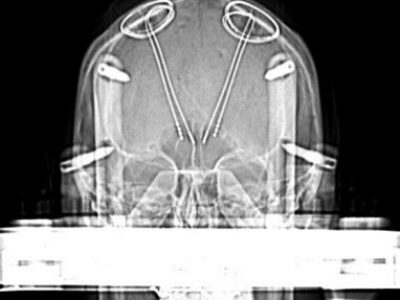

Welcome to this e-learning resource for stereotactic functional neurosurgery and DBS, with focus on visual anatomical targeting.